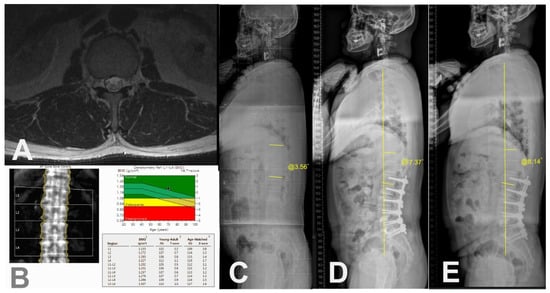

| Muscular quantity of T12-L1 (CSA of erector spinae), cm2 | 23.8 ± 4.2 | 32.2 ± 10.1 | <0.001 * |

| Muscular quality of T12-L1 (Fat infiltration in CSA of erector spinae) | <0.001 * | ||

| Mild to moderate (<50%), n | 4 | 21 | |

| Severe (≥50%), n | 13 | 3 | |

| Disc degeneration of T12-L1 | 0.923 | ||

| Mild to Moderate (Pfirrmann grade 1~3) | 7 | 12 | |

| Severe (Pfirrmann grade 4 and 5) | 10 | 12 |